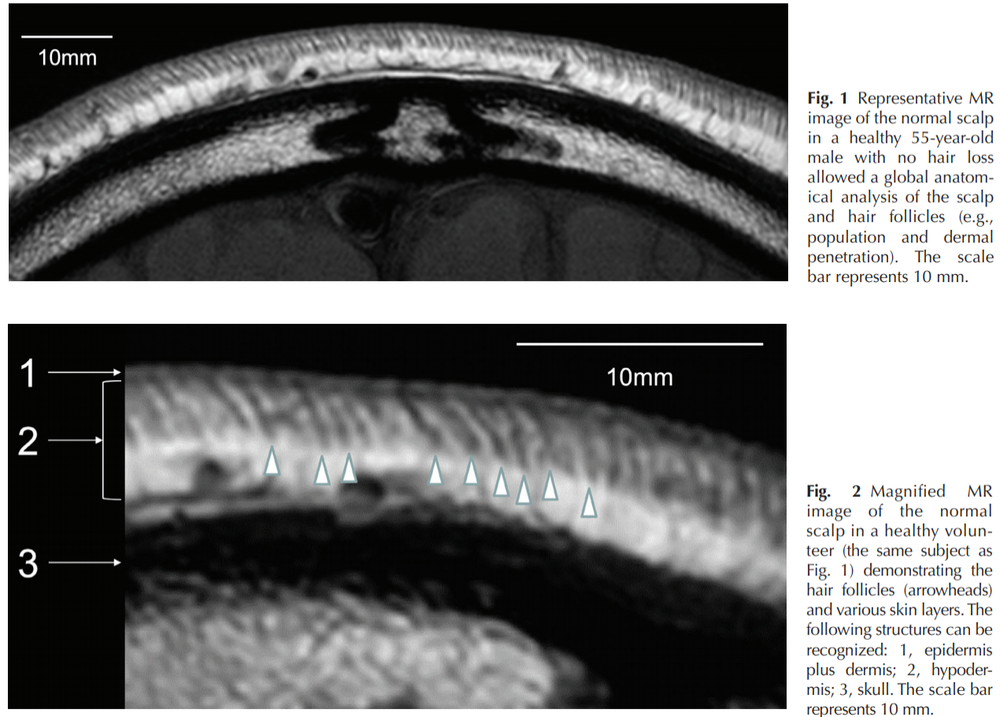

retinoic acid promotes bone profileration at the expense of cartilage(and fats).that crap destroys cartilage, induces autoantigen-homing on the hair follicle outer rooth sheath(and cartilage in the joints)- and is upregulated in balding scalps. ALso, the balding scalp has been shown to be excessively thin when compared to normal hairy scalps in MRI scans.

my analysis of this- is that bony layer, the skull(the dark matter in the MRI scan)- replaces the connective tissue above it- n that is loose cartilage. SHH ups SOX(- master regulator chondrogenesis http://genesdev.cshlp.org/content/16/21/2813.full and all things cartilage amd is a direct target of SHH.